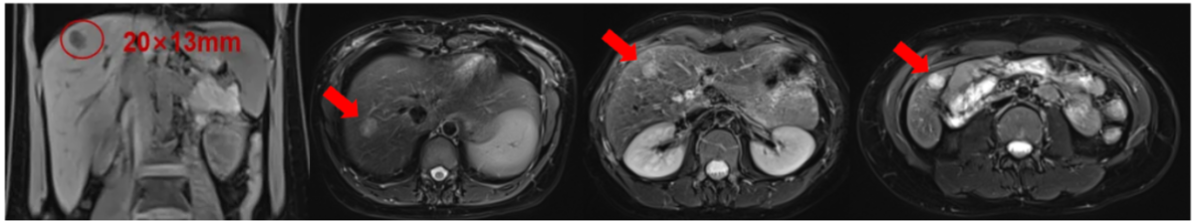

上腹部MR:肝脏多发占位(最大者位于S7,大小约20mm×13mm),考虑转移瘤可能性大。

疗效评估:右乳肿物均较前明显缩小,肝脏多发转移瘤较前缩小;部分缓解(PR)

图片 1.png

0926-02.png